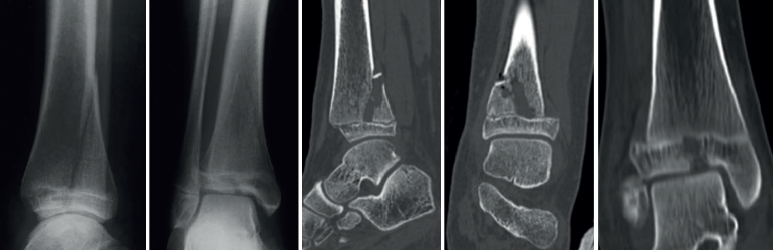

Figura 3. Imágenes radiográficas donde se ve una fractura triplanar. En la proyección lateral simula una fractura de Salter-Harris de tipo II, mientras que en la proyección coronal tiene apariencia de una fractura de tipo III o una fractura de Tillaux. Con la tomografía se puede apreciar con detalle el trazo de fractura y el desplazamiento.

La TC o la RM fueron necesarias para confirmar el diagnóstico en 13 fracturas triplanares (28,3%), 5 fracturas de Tillaux (10,9%), 4 fracturas de S-H de tipo I (8,7%), 12 fracturas de tipo II (26%), 3 fracturas de tipo III (6,5%) y 9 de tipo IV (19,6%) (Figuras 2 y 3). Del total de las fracturas de la transición, 5 fueron incorrectamente clasificadas al principio como fracturas de S-H de tipo IV y reclasificadas tras las imágenes de TC como lesiones triplanares. La mayoría de las fracturas afectaban de manera aislada a la tibia, asociando en un 23,9% de los casos fractura de peroné y en un 6,5% fracturas del tarso; mientras que en un 4,3% el trazo de fractura fisaria alcanzaba la diáfisis tibial (Figura 4).

En una radiografía simple anteroposterior, la fractura triplanar tiene apariencia de una fractura de S-H de tipo III o una fractura de Tillaux; sin embargo, en una visión lateral simula una de tipo II. Es por ello que muchas veces es clasificada erróneamente como una fractura de S-H de tipo IV(3) (Figura 3).

Para comprobar la reducción, además de valorar las proyecciones anteroposterior y lateral, es importante solicitar una proyección de mortaja para evaluar el componente vertical de la fractura de Tillaux o triplanar, que puede quedar oculto detrás de la sombra subyacente de la cortical fibular(19). Se ha demostrado que la radiografía simple resulta insuficiente para demostrar claramente el tipo, la extensión y el desplazamiento de la fractura, así como determinar el número de fragmentos(18,20). Al solicitar una TC complementaria con reconstrucción multiplanar, se minimizan los errores a la hora de clasificarlas y aumenta la precisión para cuantificar el desplazamiento intraarticular(10,19). Además, se pueden ver patrones característicos de la fractura triplanar como la estrella de “Mercedes-Benz”, que simula los 3 puntos de unión de la fractura. La RM es otra prueba alternativa que se ha utilizado para el diagnóstico de las lesiones complejas del tobillo infantil con clasificación incierta después de la radiografía simple. Ofrece la posibilidad de valorar lesiones ligamentosas y del cartílago sin irradiación. Sin embargo, el mayor gasto, los requisitos de tiempo más largos y, en algunos entornos, la disponibilidad reducida de la RM en comparación con la TC pueden limitar su utilidad en el diagnóstico de las fracturas triplanares(3,21). En nuestro caso, se solicitaron TC para el diagnóstico de urgencia, mientras que la resonancia se solicitó en 3 casos desde consultas externas para el seguimiento de la lesión. El estudio de TC fue preciso para evaluar el desplazamiento articular y además permitió reclasificar correctamente 5 fracturas triplanares que inicialmente se habían catalogado como fracturas de S-H de tipo IV. Por tanto, se recomienda solicitar pruebas de imagen complementarias a la radiografía simple en las fracturas de la transición, tanto para una clasificación correcta como para decidir y planificar el mejor tratamiento(21).